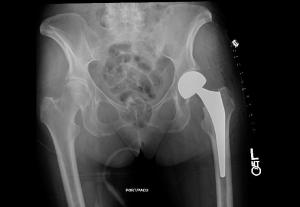

Al contrario de lo que os podáis imaginar, no es una respuesta fácil. La literatura científica no tiene grandes estudios con evidencia suficiente para poder recomendar un deporte u otro evitando grandes perjuicios para el operado. Muchas de las cosas que os voy a contar aquí estarán basadas en un artículo de la prestigiosa revista “The Journal of Bone and Joint Surgery” titulado “Athletic Activity after Total Joint Arthroplasty” (Actividad deportiva tras artroplastia total de cadera/rodilla). Aunque existen otros más recientes quizá sea actualmente la mejor guía escrita para cirujanos traumatólogos. En realidad se trata de una revisión sobre pequeños estudios basados en encuentas para intentar dar unas recomendaciones básicas sobre qué deportes podemos o no practicar tras la colocación de una prótesis total (artroplastia total, o sustitución total) de cadera y/o rodilla.

En octubre del 2007 la revista “The Lancet” de la que seguro muchos hais oído hablar por su repercusión en medicina, hablaba de la colación de una prótesis total de cadera como de la intervención quirúrgica del siglo. ¡Guau!, por encima de operaciones de cirugía cardiaca, digestiva, oncológica…etc Y lo hacía porque la gran mejoría que se produce en estos pacientes en cuanto a dolor y calidad de vida la hacen una de las intervenciones más satisfactorias que hay, pudiendo acercarse a niveles de actividad previos e incluso mejores a antes de operarse. ¿Incluye esto el hacer deporte? Paso a paso, y nunca mejor dicho. En uno de los trabajos realizados el 36% de pacientes que iban a ponerse una prótesis de cadera y el 42% de una prótesis de rodilla realizaban algún deporte antes de la intervención, a los 5 años tras ella el 52% del grupo de cadera y el 34% de los de rodilla realizaban algún deporte. Respecto a la prótesis de rodilla, como veis, los resultados todavía no igualan a los de cadera (en los que el porcentaje de actividad mejora tras la operación debido a la mayor reducción de dolor), pero de todas formas el grado de satisfacción también es muy alto.

Cuidado porque la información que se encuentra en internet, el marketing industrial (una prótesis es un producto empresarial de alta tecnología), y las opiniones sesgadas hacen que muchas personas piensen que ponerse una prótesis es como volver a ser joven otra vez. Y no es así pese a los grandes resultados. Es una intervención de cirugía mayor, que se complica poco pero que si lo hace puede ser devastadora. Evidentemente el riesgo/beneficio está muy a favor del paciente. Cada vez las personas necesitan más realizar sus actividades lúdicas y deportivas como parte de su calidad de vida, y la tolerancia a lesiones articulares es menos por la disminución en la capacidad física que producen, de ahí que cada vez se coloquen más prótesis y a menor edad. Una persona con 55 años con una prótesis probablemente desee, e incluso debe, realizar actividad física, pero cuidado, no es lo mismo jugar al golf que al baloncesto. En otro estudio se determina que las causas para no hacer deporte tras prótesis de cadera o rodilla son en un 47% precaución, 27,5% dolor en otra parte del cuerpo, y un 12,7% dolor en la articulación con prótesis. Y es que como comprobamos, los estudios a los que nos referimos son muy “generales”. Me explico, no es igual meter en la misma cesta a personas de 75 años que a personas de 50, tanto por actividad como por pretensiones, por eso los datos cogerlos con pinzas y haced mucho caso a vuestro traumatólogo.

Las superficies de contacto de la prótesis se desgastan y dependiendo del tipo de paciente usamos diferentes materiales. La durabilidad de una prótesis cada vez es mayor y será fácil que nos encontremos en el futuro a personas con una prótesis puesta hace más de 20 años. Pero es cierto que a mayor impacto mayor desgaste, y que además hay complicaciones como la fracturas periprotésicas que se deben evitar. El desgaste de la prótesis se produce por microparticulas liberadas de las superficies protésicas que se depositan en la articulación y que pueden dar reacciones inflamatorios que “aflojen” la prótesis.